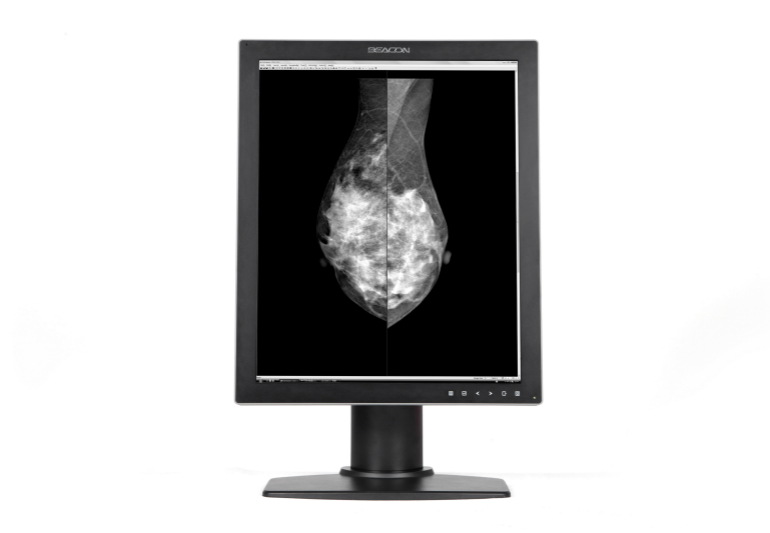

诊断显示器

临床医用显示器